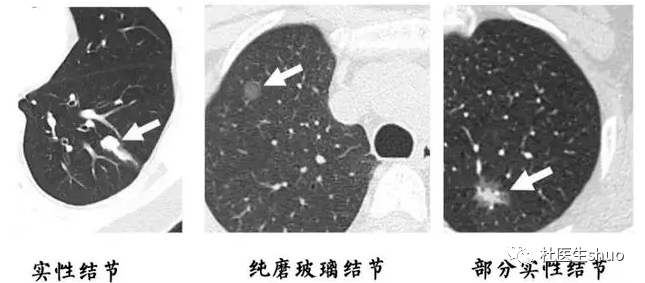

从胸部CT上看,肺部磨玻璃结节的影像表现类似磨玻璃,呈现云雾状的圆形、类圆形病灶或不规则阴影。

肺部磨玻璃结节是一种基于密度改变的影像学表现,只要是引起肺泡腔充气程度的任何改变,都可以在CT影像上形成磨玻璃结节。

磨玻璃结节只是影像学上一种客观的描述,不代表疾病本身或者预示着病情走向。